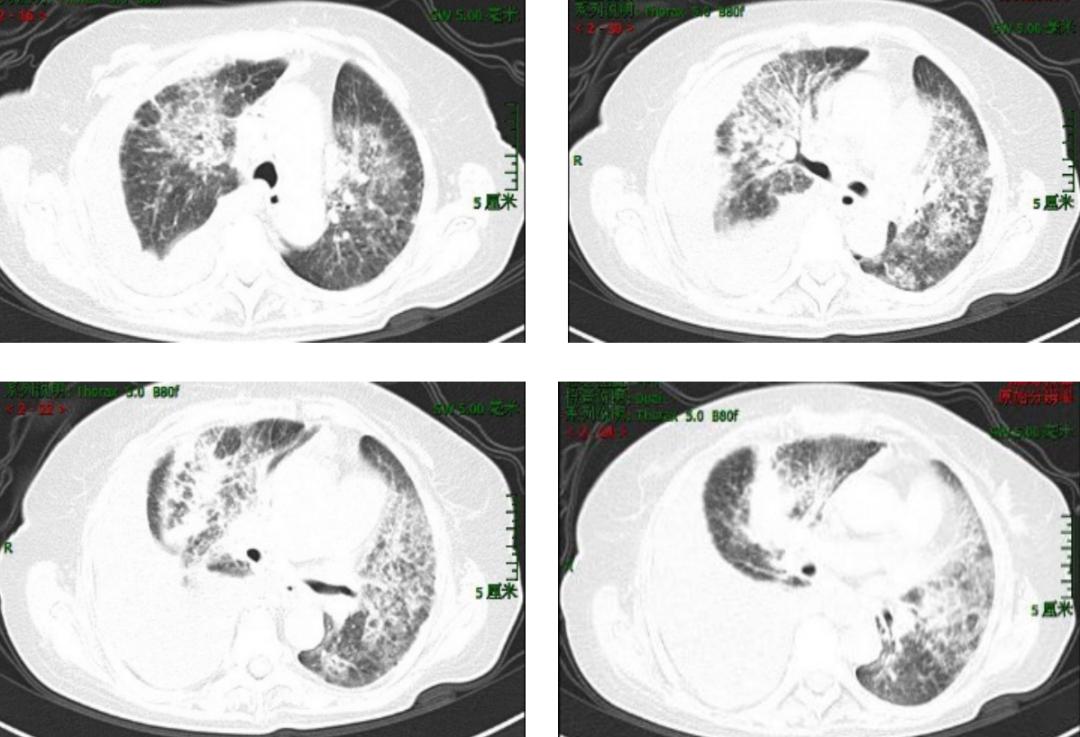

胸部增强CT(2017-02-14):双肺内多发斑片影、蜂窝状影及结节影,伴双肺气管、支气管壁稍增厚,考虑炎症,建议治疗后复查。右侧胸膜腔大量积液。右肺中下叶压迫性肺不张。纵隔及双肺门多发淋巴结钙化。胸主动脉及双侧冠脉钙化。腹水。CTPA:右肺下叶肺动脉未见明显显影,左肺下叶肺动脉显影较差。余肺动脉未见明显充盈缺损。

图1:胸部CT(2017-02-14)提示双肺斑片影、蜂窝状影及结节影,伴双肺气管、支气管壁稍增厚、右侧大量胸腔积液。